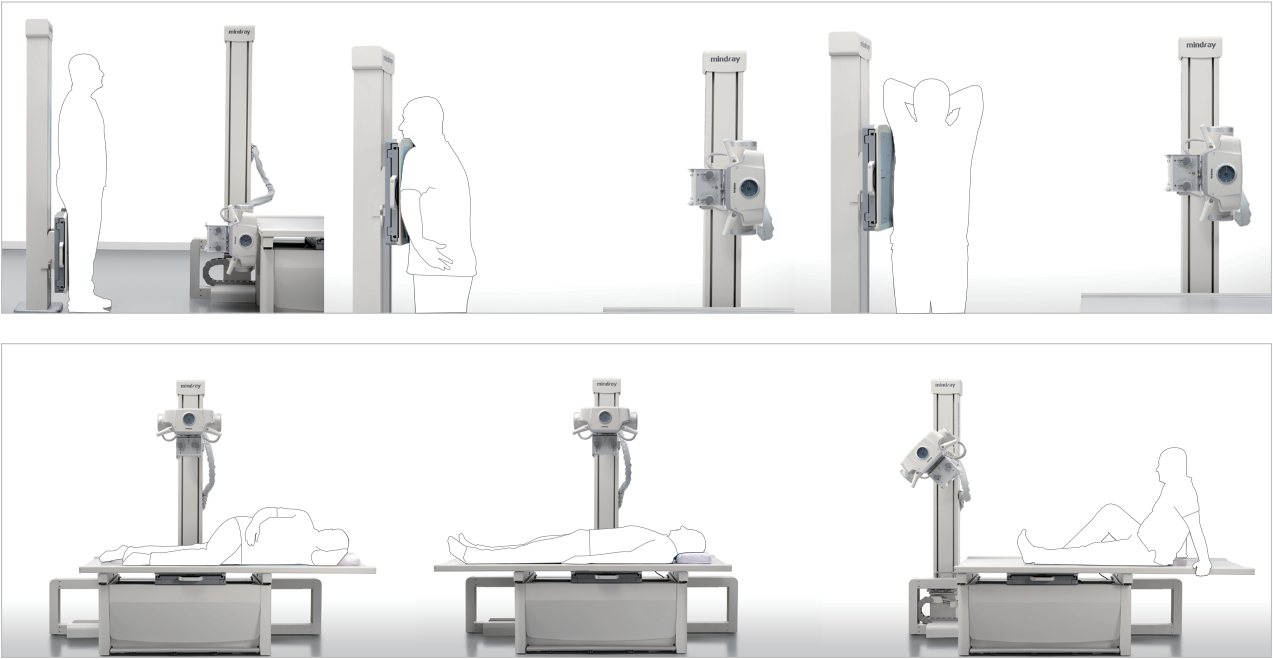

Posicionamiento flexible y eficiente:

El posicionamiento es el mismo que con la radiograf├Ła convencional y no se produce ning├║n cambio al respecto.

Es posible cambiar con rapidez de una posici├│n horizontal a una vertical. Adem├Īs, la mesa flotante fija permite reducir en gran medida el tiempo necesario para mover a los pacientes y mejorar el rendimiento.